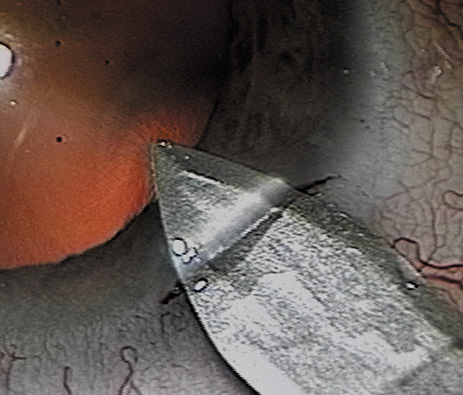

There are several ways to fashion a clear corneal or near-clear corneal incision. The incision can be a single-plane stab into the anterior chamber. However, a two- or three-plane incision may create a more secure wound. The external and internal portions of the incision should be straight lines, tangential to the limbus. Shorter tunnels allow for better visualization and facilitate phacoemulsification handpiece maneuverability, whereas longer “squarer” tunnels have been shown to have higher wound rupture pressures.93 The surgeon must weigh these issues when selecting the tunnel length. Special incisional architectures also work well, including hinged incisions, where the external groove is deeper than the tunnel and trapezoidal incisions.94,95 The authors prefer to make a groove perpendicular to the corneal surface at the most peripheral aspect of cornea, where the incision will just engage limbal vessels. A guarded blade set at 300 to 550 μ works well. Then a keratome is used to tunnel the incision forward within the corneal lamellae before angling the keratome slightly more posteriorly to pierce Descemet's membrane (Fig. 9). Regardless of the technique used to fashion the incision, it is important that the surgeon does not over-manipulate the anterior lip of the incision because such trauma may result in a poorly sealing wound at the end of the case. Also, when inserting an instrument or IOL through the incision, be certain that pressure is directed posteriorly and the incision is of adequate size to avoid stripping Descemet's membrane. Clear corneal incisions are best suited for injectable or foldable IOLs.

Fig. 9. A dual beveled metal keratome (Alconlabs, Ft. Worth, TX) is used to fashion a 3.0-mm near-clear corneal incision.